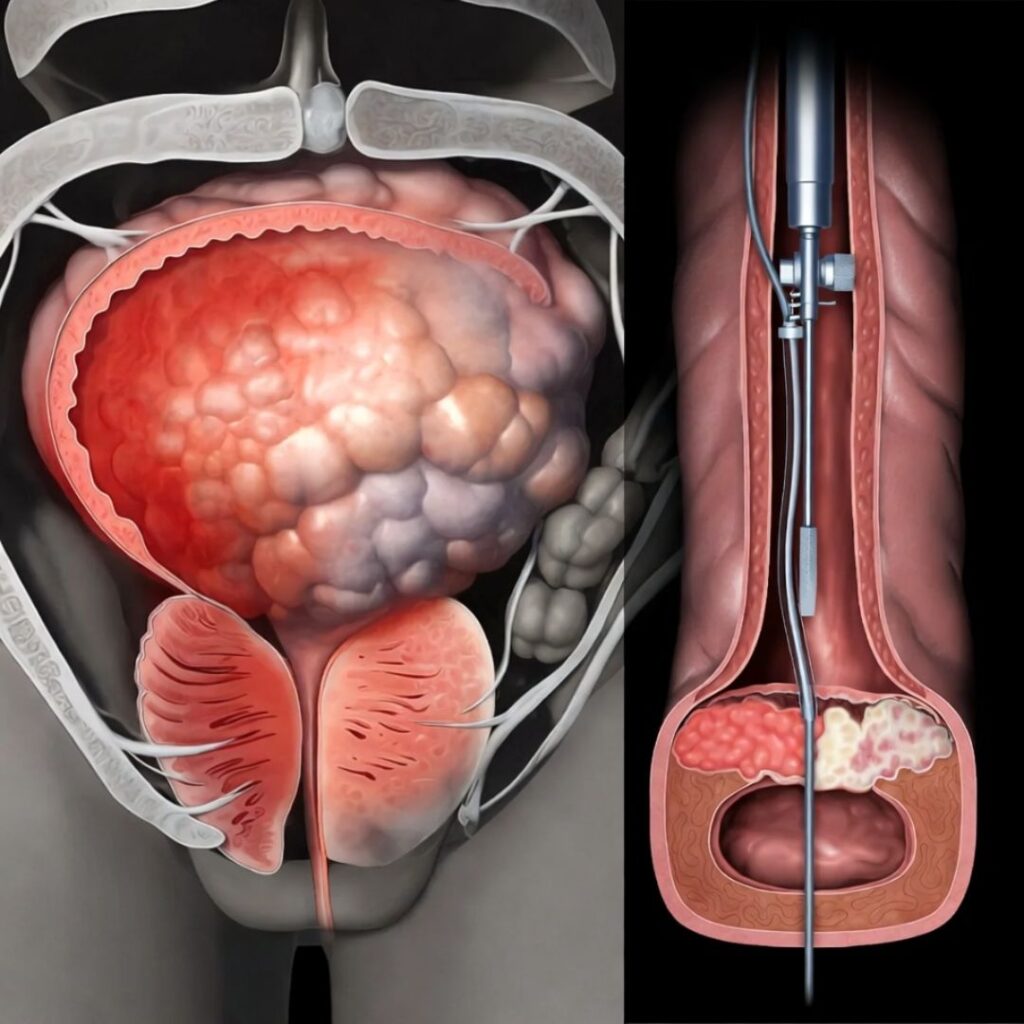

Deep inside your pelvis — wrapping around your prostate gland, threading along the base of your penis, and extending in a dense web of fibres all the way to the nerve endings at its tip — there is a network of nerves. Medical textbooks call it the cavernous nerve system. Think of it, for the purposes of this conversation, as the electrical wiring of your sexuality.

When you experience arousal — when your brain processes a touch, an image, a memory, a smell — it sends an electrical signal. That signal travels down your spinal cord, branches out through your pelvic nerves, and arrives at the cavernous nerve network. From there, the nerves release a chemical called nitric oxide. Nitric oxide causes the smooth muscle tissue inside the penis to relax. Blood floods in. The tissue expands. You have an erection.

CAUSE THREE: PROSTATE INFLAMMATION AND SURGERY

The prostate gland sits immediately adjacent to the cavernous nerve bundle. It is, anatomically, neighbours with the wiring that controls your erections.

Chronic prostatitis — persistent inflammation of the prostate — creates sustained mechanical pressure on those nerves. Over time, this pressure disrupts nerve conduction in the same way that sitting on your arm for too long causes it to go numb — except that the effect is permanent rather than temporary, because the nerve fibres themselves are being physically compressed and chemically irritated over years.

Prostate surgery — including the increasingly common robotic prostatectomy — carries a documented risk of cavernous nerve damage even when performed by the most skilled surgeons. Men are typically told, post-surgery, that “some degree of erectile dysfunction is normal and may improve over time.” What they are rarely told is that without active nerve rehabilitation, the improvement rate drops dramatically.

It is a precision electrostimulation device. It generates a specific pattern of low-frequency electrical pulses — calibrated to the exact therapeutic parameters of Dr. Mercer’s fourteen-year research programme. Those pulses are delivered through a contact interface to the perineal and penile surface, where they stimulate the cavernous nerve network.